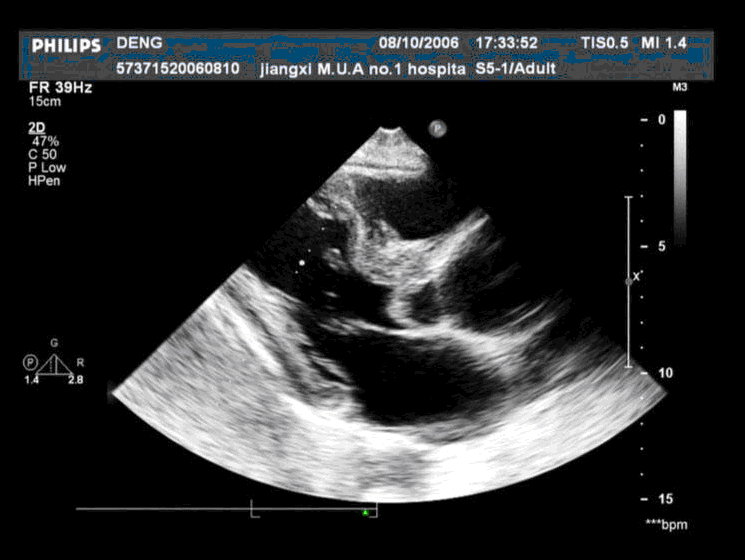

患者,男,50岁,发热半月余,全身不适,乏力,食欲缺乏。根据超声心动图,最可能的诊断是 CF20160315_19.gif CF20160315_20.gif CF20160315_21.gif CF20160315_22.gif

• B.感染性心内膜炎